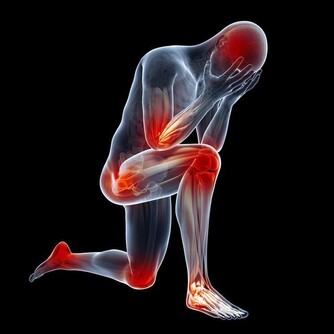

跌倒不但會造成腦部受傷、骨折等嚴重外傷,還會引發“跌倒恐懼症”,給老人帶來極大的心理創傷。

跌倒損傷最嚴重的是髖部骨折,成為老年人首位傷害死因。

另外會造成顱腦損傷,可直接導致死亡。